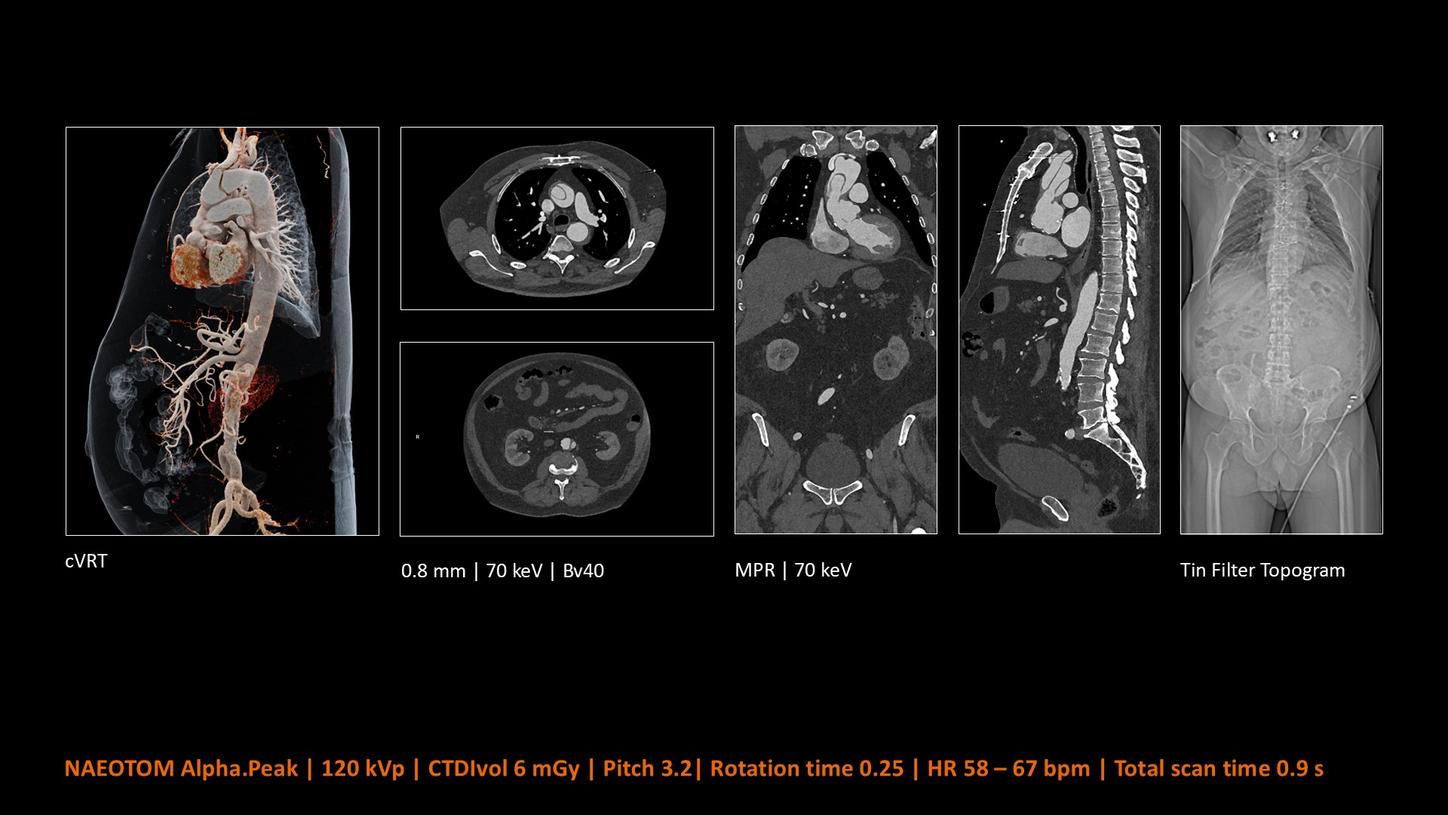

NAEOTOM Alpha® con Quantum Technology®, la nostra nuovissima Dual Source photon-counting CT, offre immagini Quantum HD Cardiac con uno spessore di slice di 0,2 mm. In questo modo è possibile visualizzare dettagli del cuore precedentemente non rilevabili senza incrementi di dose. Inoltre, le informazioni spettrali sono automaticamente disponibili in ogni scansione grazie a un processo di conversione diretta che trasforma i singoli fotoni dei raggi X in un segnale elettrico per creare l'immagine.

Inarrestabile in ambito cardiovascolare